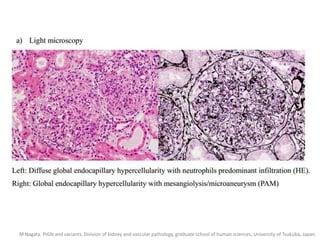

Pathological appearance

• Base on the glomerular change…

– Proliferation of mesangial, endothelial and epithelial cells,

inflammatory exudate and early deposition of C3 then IgG.

• Immune deposition classified into 3 patterns.

– Starry Sky pattern.

– Garland pattern.

– Mesangial pattern.

Sorger, K., et al., Subtypes of APIGN. Synopsis of clinical and pathological features. Clin Nephrol, 1982. 17(3): p. 114-28.

M Nagata. PIGN and variants. Division of kidney and vascular pathology, graduate school of human sciences, University of Tsukuba, Japan.